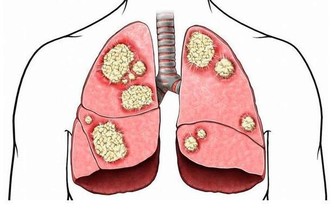

冠心病是冠狀動脈性心髒病的簡稱,是一種由于冠狀動脈固定性(動脈粥樣硬化)或動力性(血管痙攣)狹窄或阻塞,發生冠脈循環障礙,引起心肌氧供需之間失衡而導致心肌缺血缺氧或壞死的一種心臟病。

冠心病主要有心絞痛和心肌梗死兩類

心肌梗死是由冠狀動脈分支血管斑塊突然破裂導致的急性閉塞所致,常伴有長時間(一般超過30分鐘)的胸悶、胸痛等症狀,有的還會出現上腹疼痛、噁心、嘔吐等,嚴重者可發生心室纖顫,出現意識喪失、抽搐,甚至死亡。